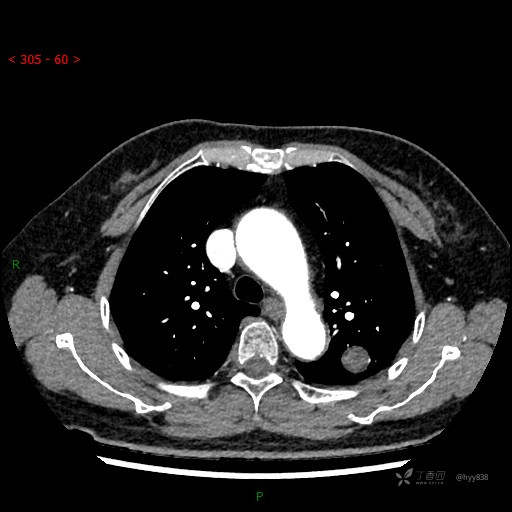

增强动脉期

各期CT值:28hu、58hu、69hu